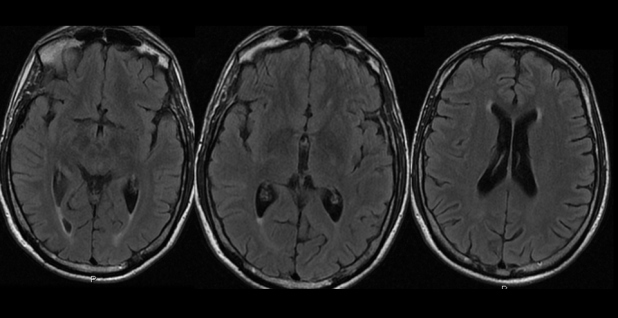

En la resonancia magnética (RM) se encontró discreto aumento del espacio extraaxial y del sistema ventricular supratentorial, secundario a atrofia parenquimatosa córtico-subcortical dependiente de la edad (fig. 1).